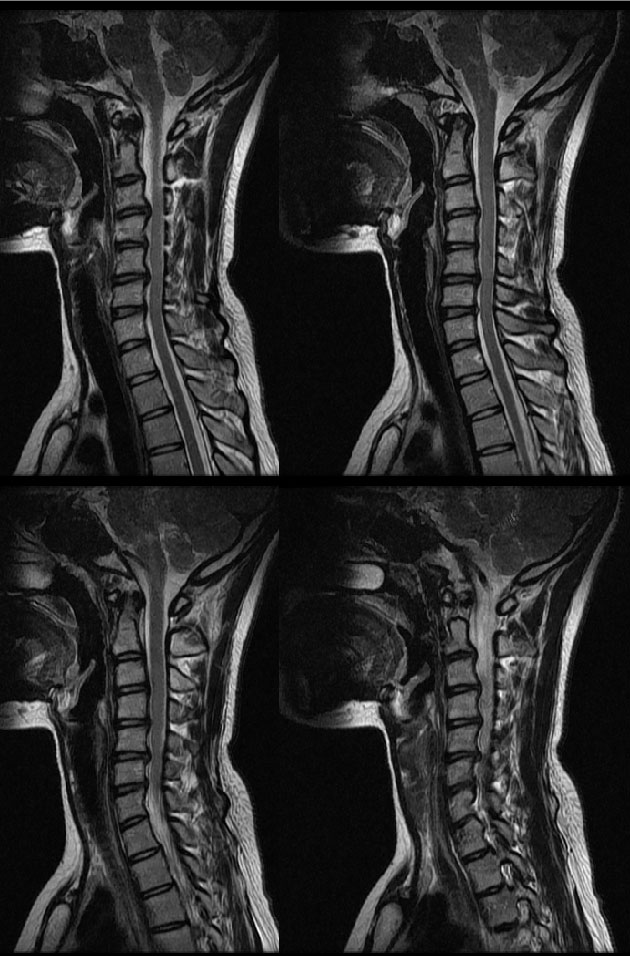

##ȣ@% mriԳ. Ͻð ⸮ ֵ帮 Ű162 53 22 ˰Ե ͳ õ ͳ ˻ڷ õ ##ȣ@% ش 1C.ڵ, 1C., 1C.ڵӸ 1C.ٽŰ 1C.ٿ, 1C. 1C.ٺҸ, 1C.پǸ, 1C.ٽŰ, 1C.ٸǷ 1C., 1C.ھ 1C.ں 1C.ټ Ǹ 1C.ٱ () 1C.߷ () 1C.Ƿ () 1C. , 1C.ٰ , 1C.ٳ 1C.ڱ ֺ 1C.2C.3C.١ڻ浿 2C.ھȱ, 2C.ٴ, 2C.ٸ 2C,3C,ΰ 3C.帧 4C. 4C.û° 4C.5C.ھ, հ 5C.ٸ, 5C.εο, 5C.ĵο, 5C.6C.ڰ հ ̳ 6C.ڸ 6C. κ 6C.ھ Ḳ 6C.ڻ 6C.7C.ھ հ ̳ 7C.ڿʰ 1T.ڼհ ü ̳ 1T. κ 3T.ڵ , 4T.Ȳ 5T.ȯ ҷ, 5T.ھ ȯ 11T.ٳġ 帧 11T.ȯ 12T.ٰ () 1L. 3L.ڽѻ Ǵ Ҽ 3L.汤, 3L.̻ 3L. 3L.ڹ 5L. , 5L.Ƹ 㰡 õ().شٸ (). ġ ()ũ( ߰Ż) ڸ(߹) ĿCڸ(ĸ) Ը Ͽ ũ(߰Ż)ġ, հ , ġ, , Ḳ ġ Ǵ , , ȱ ǰϰų ڸ, , ڰ , , Ǵ ġ ʰ, װ Ǵ ġ Ҹ ġ ħ , ġ ħ ߷, , нɷ Ʈ 氨 Ǻι̿, Ǻγȭ Ƿ ġ ϰ Ѱ ְ Ʈ ϰ ϴ ġ ->->հ ϴ ġ ũ ġ |